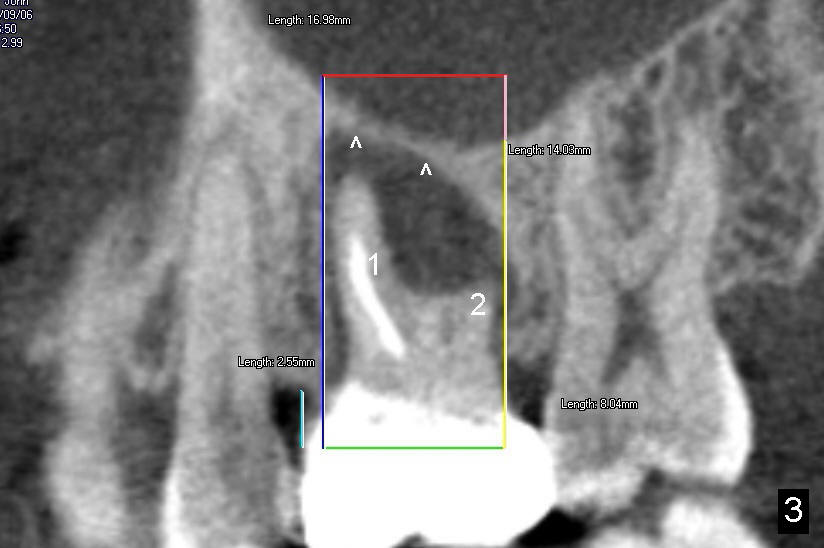

The tooth #3 of a 40-year-old man has endo failure (Fig.1-4) with resorption of the mesiobuccal plate (Fig.2). Ideally a 8x17 mm cylindrical implant is placed immediately post extraction (Fig.2,3). The patient wants to remove the tooth first and wait until his insurance gets approval for the implant coverage. No bone graft is placed in the extraction socket.

Following local anesthesia, the failing implant is removed without resistance. The sinus floor is present. The lateral walls are intact, although probably short. A series of rounded tapered osteotomes (2-5 mm in diameter) are used for sinus lift at the depth of 14 mm. A 4.5x14 mm tap is inserted (Fig.10). One more carpule of Lidocaine is administered. A 6x14 mm implant is placed with torque more than 60 Ncm without additional bone graft (Fig.11). A 6-month postop PA confirms osteointegration (Fig.12). An abutment is placed (Fig.13) for a definitive crown (Fig.14). PA taken 6 months post cementation shows that bone density mesial to the implant increases (Fig.15 <).